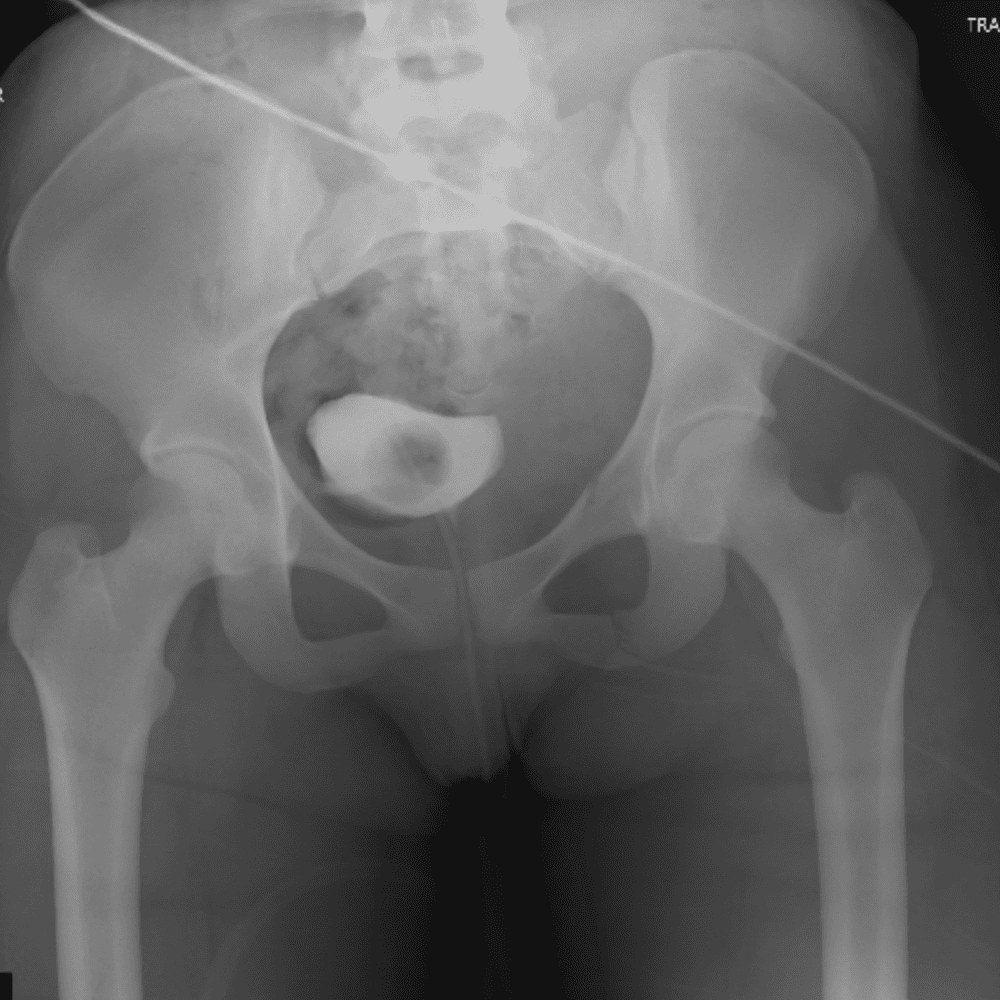

通过包含微妙或困难的病例和一些正常病例来模拟值班。

30 病例